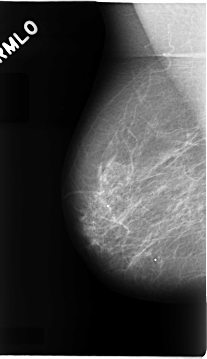

C_0072_1.LEFT_MLO

LEFT_MLO LINES 4696 PIXELS_PER_LINE 2664 BITS_PER_PIXEL 12 RESOLUTION 50 OVERLAY